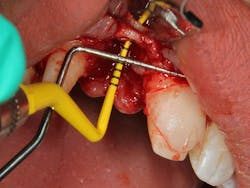

Related video: Extraction and socket grafting in preparation for dental implant placement

This surgical video demonstrates removal of a tooth with loss of buccal plate and grafting of the remaining socket with Geistlich Bio-Oss Collagen and Geistlich Bio-Gide to preserve the ridge for implant placement.